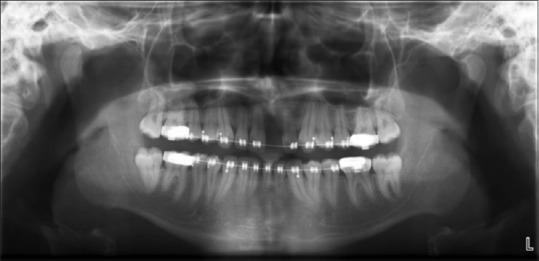

Bone defects at the anterior regions of the jaws often cause esthetic problems such as gingival disharmonies and longer crowns than neighboring teeth. Variety of procedures can be used in this region for achieving sufficient bone volume with or without different bone graft materials. All of these procedures has their own advantages and disadventages. New bone formation was defined with orthodontic tooth movement in different regions. In this case we present the use of orthodontic tooth movement, for achieving sufficient bone volume, in anterior maxillary region, for esthetic and functional results.

颌骨前部的骨缺损常常会导致美观问题,如牙龈不协调以及牙冠比相邻牙齿长。在该区域可采用多种方法,无论是否使用不同的骨移植材料来获得足够的骨量。所有这些方法都有其自身的优缺点。在不同区域,正畸牙齿移动可促进新骨形成。在此,我们介绍在前上颌区域利用正畸牙齿移动来获得足够的骨量,以实现美观和功能效果。